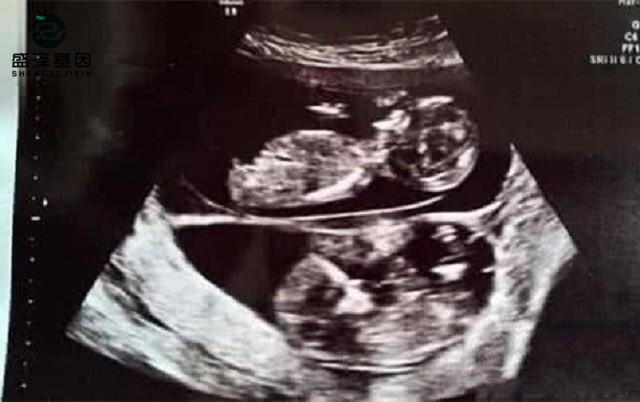

當妻子的肚子漸漸大了,阿杰帶妻子去做B超的時候,得到了一個更加令他欣喜若狂的消息:妻子懷的是雙胞胎!

不過,有些雙胞胎確實會長得不一樣。因為雙胞胎的淺層含義,就是一胎有兩個胎兒。通常情況會分同卵雙胞胎和異卵雙胞胎。

同卵雙胞胎就是一個受精卵分化成兩個胎兒,所以他們的長相幾乎一模一樣,只是會有細微的、不易察覺的區(qū)別。

而異卵雙胞胎則是母親的兩個卵子同時和父親的兩個精子結(jié)合成受精卵。同一胎會有不同長相、不同性別的顯著性狀出現(xiàn)。